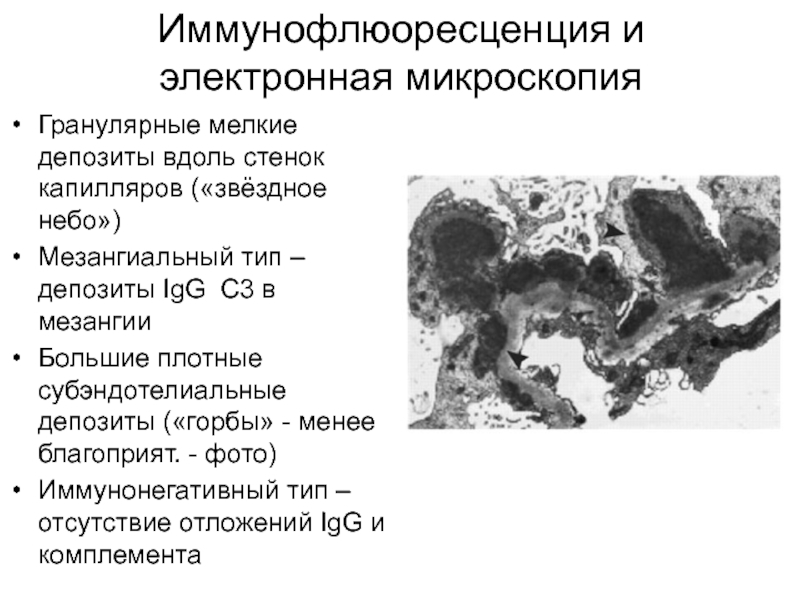

Симптомы подострого гломерулонефрита: фото и описание

Раздел: Визуальный дайджест